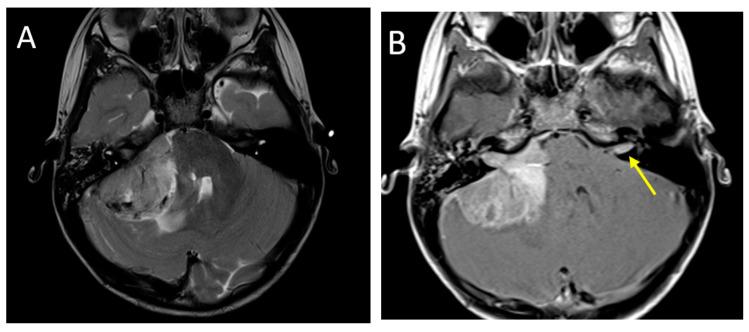

Primary brain tumors are the most common solid neoplasms in children and a leading cause of mortality in this population. MRI plays a central role in the diagnosis, characterization, treatment planning, and disease surveillance of intracranial tumors. The purpose of this review is to provide an overview of imaging methodology, including conventional and advanced MRI techniques, and illustrate the MRI appearances of common pediatric brain tumors.

原发性脑肿瘤是儿童中最常见的实体肿瘤,也是该人群死亡的主要原因。磁共振成像(MRI)在颅内肿瘤的诊断、特征描述、治疗规划和疾病监测中起着核心作用。本综述的目的是概述成像方法,包括传统和先进的MRI技术,并阐述常见儿童脑肿瘤的MRI表现。